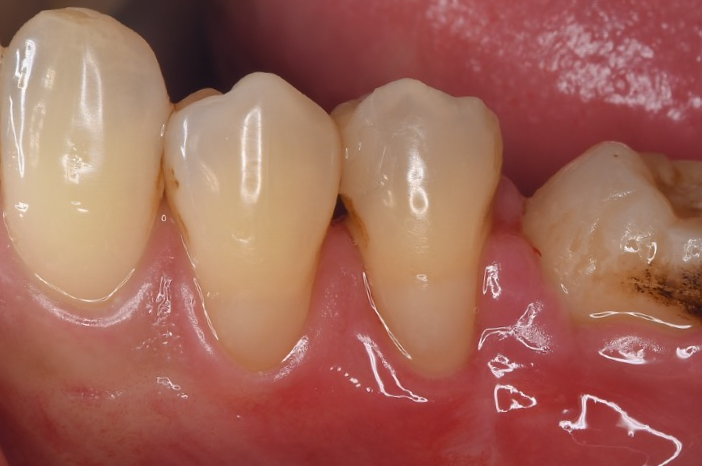

症例3

| 項目 | 詳細 |

|---|---|

| 患者様データ | 50代 男性 |

| 来院時の主訴 | 「左下の歯が歯磨きでしみる。」 |

| 医院の診断 | 歯肉退縮・歯周病(根分岐部病変) |

| 通院期間 | 1年 |

| 来院回数 | 12回 |

| 治療費 | 総額:630,000円(税抜) 【内訳】 歯周組織再生療法220,000円 歯肉結合組織移植術170,000円 セラミック治療120,000円×2 |

| リスクと副作用 | 定期的なメンテナンスが必要、術後若干の腫れと痛み |

| ここがこだわりのポイント!☝ | 歯周病と歯茎下がりを同時に解決しました。歯肉の厚みが増したことで、歯磨きがしやすくなり、歯がしみる症状も改善しました。 |